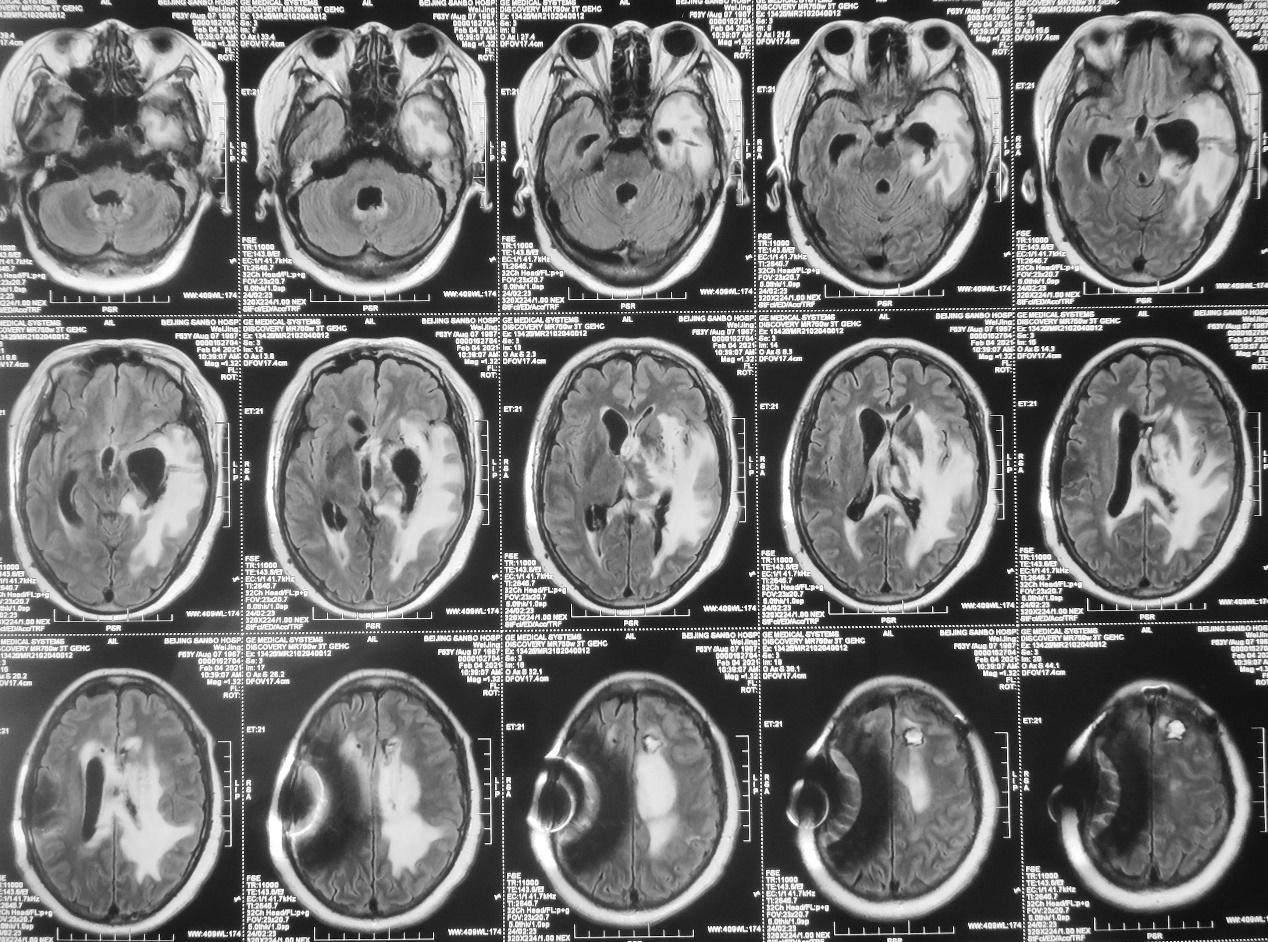

患者体温正常,仍呈朦胧状态,可自动睁眼,刺激肢体可活动。脓肿清除术后第13天,左侧颞角外引流术后第12天,右侧脑室穿刺术后10天,即2020年12月21日,复查头颅核磁( 图-16 )见脑室缩小,丘脑脓肿病灶缩小,左侧脑室枕角和小脑表面的强化灶消失,提示颅内感染好转。

图-16: 2020年12月21日头增强核磁

经治疗后患者发热好转,神志清醒,于第3次左侧脑室颞角引流后6天,即2021年2月1日,拔除了左侧颞角引流管。但发病后88天,即脑脓肿清除术后第59天,脑室腹腔分流术后第23天,拔除左侧颞角引流管后3天,即2021年2月4日,患者再次发热,体温38.3℃。患者间断嗜睡,复查头颅核磁共振( 图-29 )提示左侧脑室颞角扩张。于2021年2月4日,当天行第4次左侧脑室颞角穿刺外引流术。

图-29: 2021年2月4日头核磁

术后第8天,即2021年2月18日,复查头颅CT见右侧脑室缩小,左侧脑室稍扩张( 图-34 )。脑脊液细菌培养结果回报为表皮葡萄球菌,但患者无发热,神志逐渐好转,由入院时的刺痛睁眼好转为可自动睁眼,左侧肢体可遵嘱活动( 图-35 )。

图-34: 2021年2月18日头CT

脑室腹壁外引流术后第1天,即2021年2月25日,复查头颅CT见脑室系统缩小,左侧脑室颞角较前无明显变化,左侧脑室颞角及三角区周围仍明显水肿( 图-38 )。患者病情稳定,可遵嘱动作,但反应稍慢( 图-39 )。

图-38: 2021年2月25日头CT